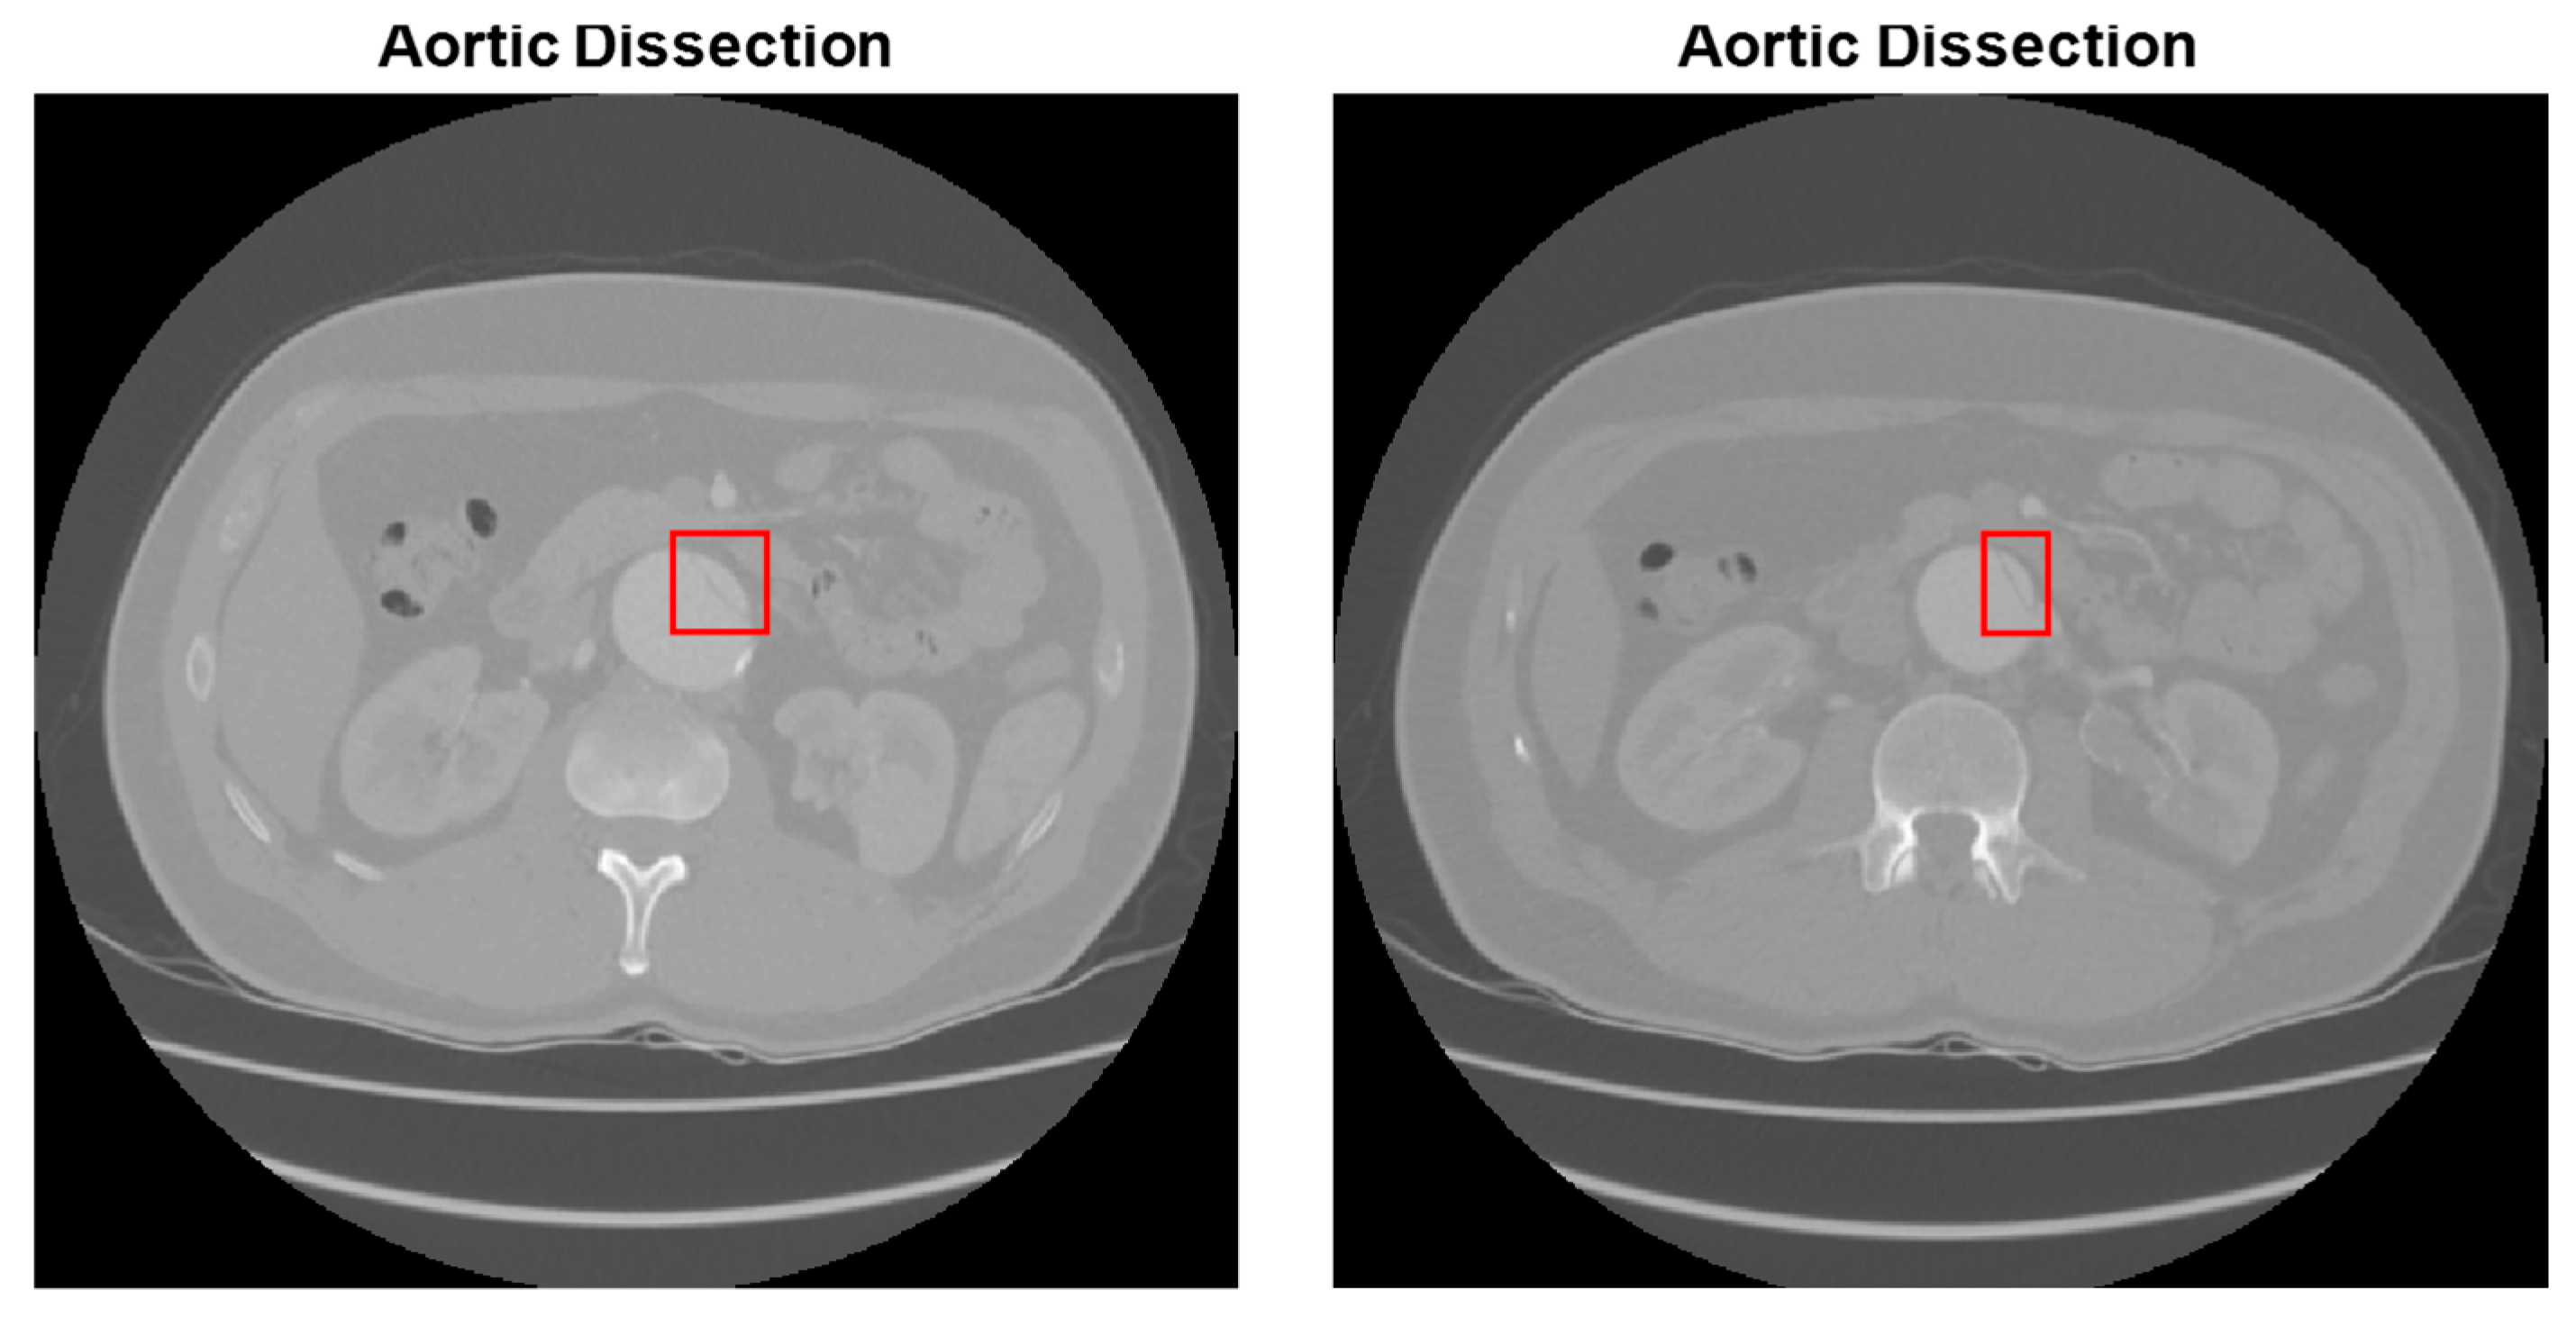

2.3. Abdominal Aortic Dissection (AAD) Detection